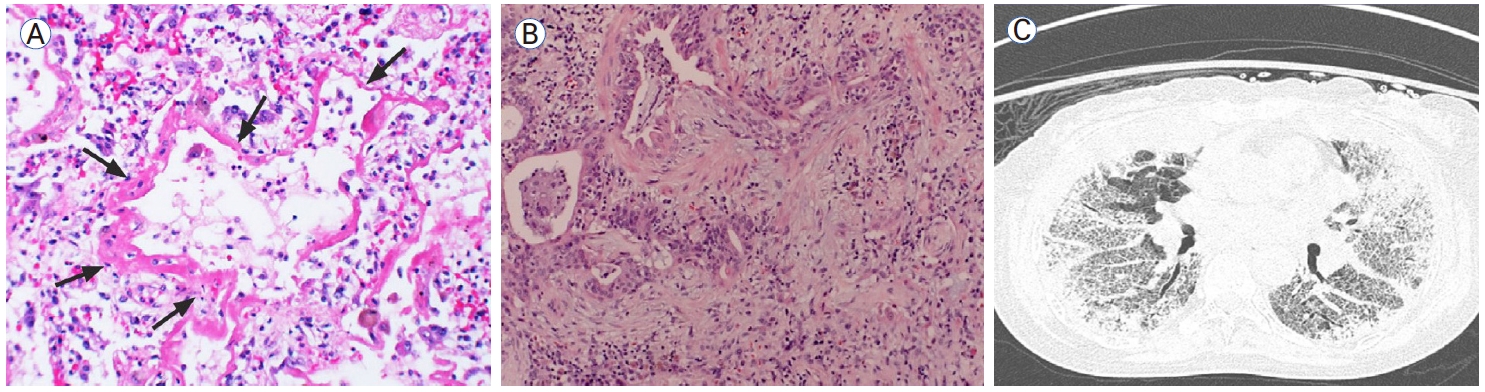

Radiological-histological patterns |